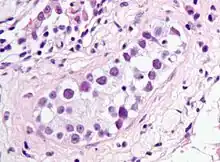

ITGCN. H&E stain.

GCNIS is not palpable, and not visible on macroscopic examination of testicular tissue. Microscopic examination of affected testicular tissue most commonly shows germ cells with enlarged hyperchromatic nuclei with prominent nucleoli and clear cytoplasm. These cells are typically arranged along the basement membrane of the tubule, and mitotic figures are frequently seen. The sertoli cells are pushed toward the lumen by the neoplastic germ cells, and spermatogenesis is almost always absent in the affected tubules. Pagetoid spread of GCNIS into the rete testis is common. Immunostaining with placental alkaline phosphatase (PLAP) highlights GCNIS cell membranes in 95 percent of cases. OCT3/4 is a sensitive and specific nuclear stain of GCNIS.[3]